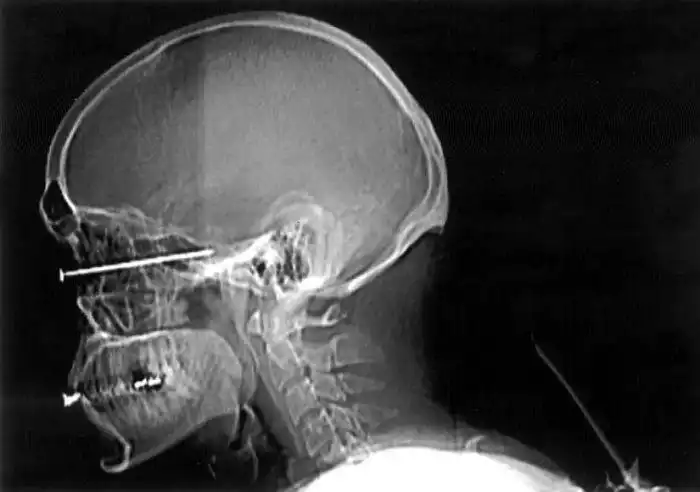

Необычные предметы в теле людей на рентгеновских снимках

На рентгеновских снимках людей порой можно обнаружить самые необычные предметы, которые находятся в их теле.

Человечество явно с гвоздями не дружит!!! Что не снимок то гвоздь в башке!